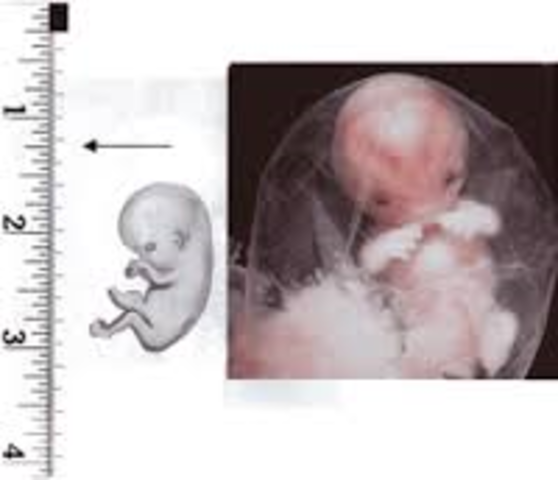

• Week 5

Week 5

The embryo now starts the process of shaping into a human. The placenta is developing and amniotic fluid begins to build up whcih will surround the fetus. The embryo is about 2-5mm.